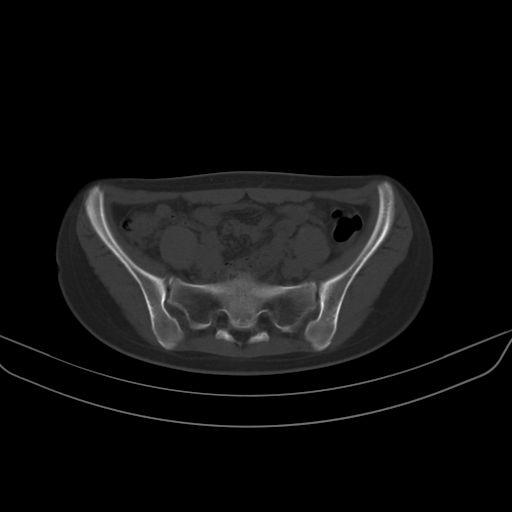

以下是引用子十在2008-7-11 21:12:00的发言:[br]考虑强脊

以下是引用zsl6918在2008-7-11 21:40:00的发言:[br]双侧骶髂关节骨质破坏以下三分之一为主,符合强直性脊柱炎表现

以下是引用zhangzhongshou在2008-7-11 21:41:00的发言:[br]患者是女性,hla-b27抗原(—),首先不太考虑强直性脊柱炎,建议查类风湿因子,骶髂关节改变考虑类风湿性关节炎可能性大,建议进一步检查。